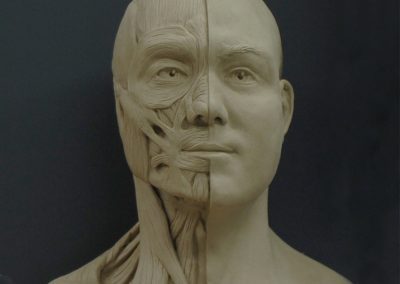

A strong Vertebrate Anatomy lecture class combined with a hands-on dissection lab will help prepare applicants for the science courses taken during the CA program. Learning anatomical terminology and scientific names is encouraged. Artists who have hands-on experience with dissection develop a tactile memory for the different organs, textures, locations and inter-relationships that will inform knowledge of those structures. While hands-on, student-performed, whole specimen, vertebrate dissection labs are encouraged, alternate labs are acceptable (see below).

Histology is the study of the different tissues of the human body at the microscopic level. Understanding the structures of the human body from the macroscopic (Anatomy) to the microscopic (Histology) levels will aid in anaplastology treatment planning.

Cancer, birth differences and traumatic incidences, the most common reasons patients seek the care of clinical anaplastologists, will impact different tissues in the body: bone, skin, muscle. Having a microscopic understanding of these tissues could influence patient care.